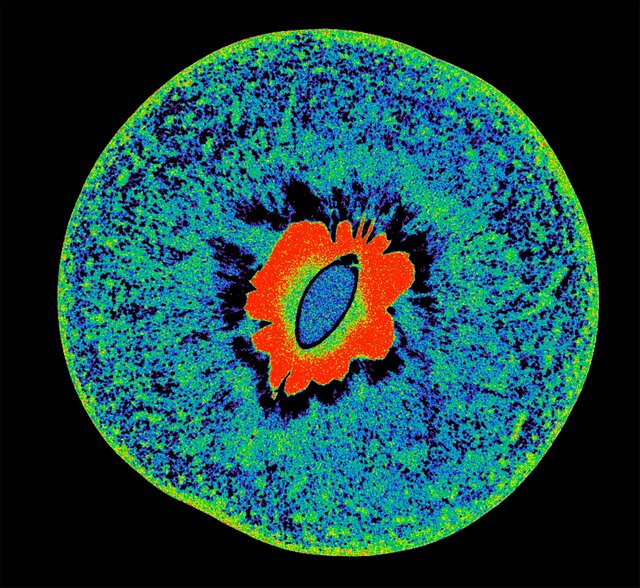

این تصویر ممکن است شاد به نظر برسد، اما ما به شما اطمینان میدهیم که اینطور نیست. این تصویر میکروسکوپ فلورسنت، دامنهی اتصال گیرندهی پروتئین اسپایک سارس-کو-۲ ویروس عامل بیماری کووید-۱۹ را نشان میدهد.

عکس: هارشیتا روپانی(Harshita Rupani)